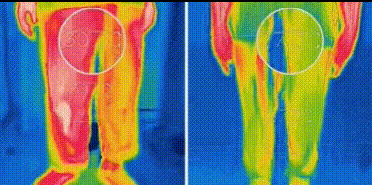

想要清涼一夏嗎 這款休閒冰絲五分褲是你的不二之選 輕薄透氣的面料 穿上它彷彿置身涼爽之地 輕鬆告別悶熱